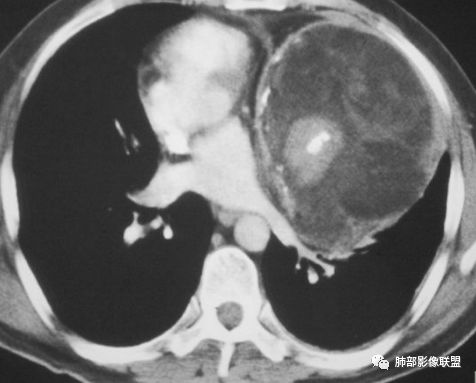

纵隔或胸膜伴钙化疾病谱(吴婧):A:异位甲状腺——最常见,甲状腺癌非常容易钙化,一般与甲状腺相连,平扫因为摄碘,CT值很高,增强后则明显增高。B:畸胎瘤——脂肪、牙齿密度可识别。一般多发年轻30岁左右,钙化特点为块状钙化少见,环状钙化多见,钙化不在中间(偏心钙化)。很少强化或轻度强化                            (王兆宇老师)C:CD透明细胞型——一般钙化为条状钙化,病灶形态通常为圆形、光滑、规则、全实性,不软所以不会见缝就钻,也不会坏死,强化非常高。D:胸腺瘤——一般30岁以后,容易钙化为A、AB、B1型,B2型以后钙化少见。钙化特点为大块状钙化、中间钙化。E:SFT——钙化会沿着胸膜的长轴生长。

大部分钙化还是包膜钙化和条状,结节状钙化,团块状钙化也比较少。位置中央,周围都可以。